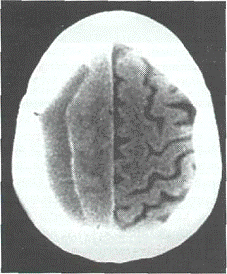

Представим следующее компьютерно-томографическое

определение ХСГ: хроническая субдуральная гематома представляет собой зону

измененной

плотности между костями черепа и веществом

мозга, обычно серповидной формы с многодолевым распространением и

преимущественно парасагитально-кон-векситальной локализацией; при этом наружная

граница повторяет очертания внутренней поверхности костей черепа, а внутренняя

граница - очертания полушария мозга (рис.3).

Рис.3 Типичная КТ картина ХСГ (1,2).

Трехмерная КТ реконструкция этой ХСГ (3,4).